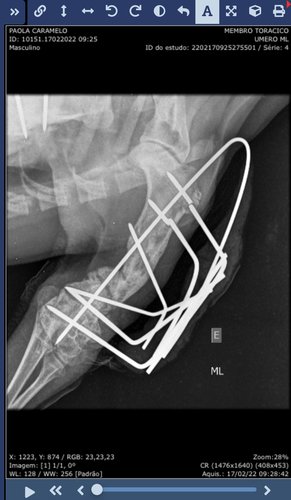

No dia 17/02 realizamos um novo raio x, e infelizmente não tivemos boas notícias. Mesmo após 3 meses da última cirurgia, as fraturas do Caramelo seguem sem nenhuma melhora na cicatrização, além de alguns pinos terem quebrado dentro dele.

Imagens e laudo do raio x: